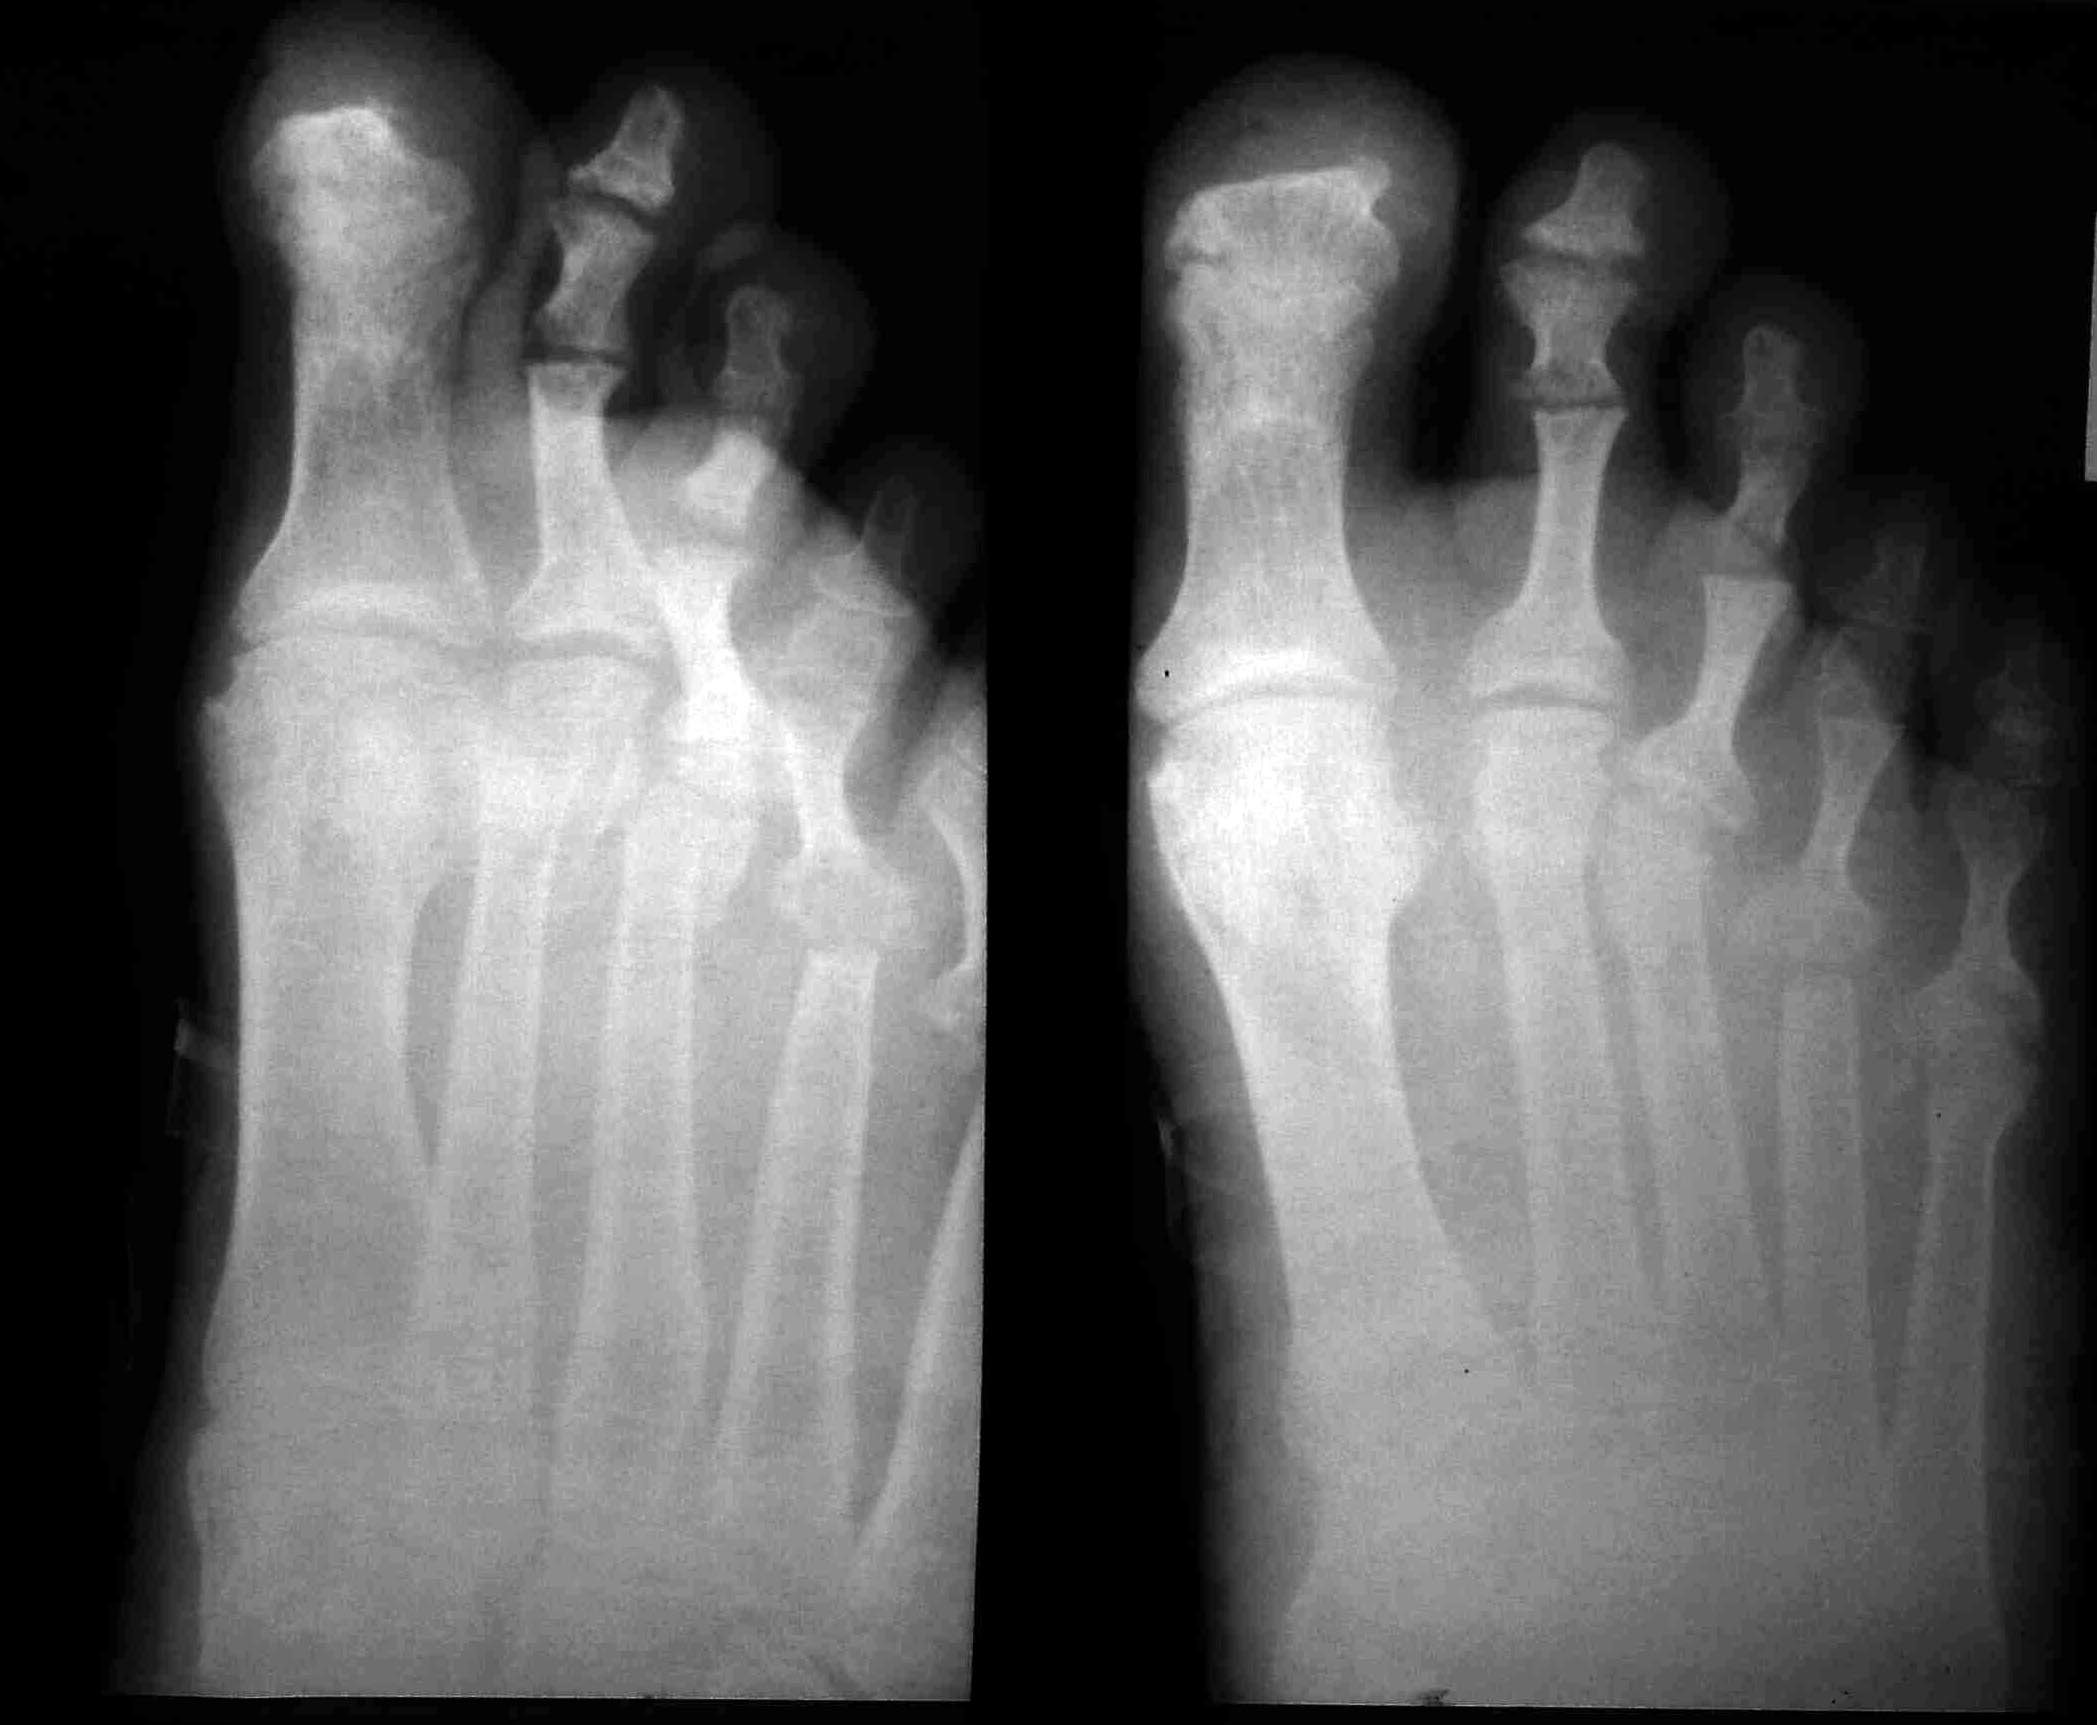

продолжение темы http://weborto.net/forum/1356148170/index_html Послеоперационные снимки (извините за качество), выполнены: Weil - 2,3, резекция головки - 3, резекция проксимальных м/ф суставов(костный анкилоз). Действительно, в первом пальце есть переразгибание, но - не ригидное, пациент на нем вмешиваться отказался. В приложении - предоп рентген в качестве получше и постоп (еще раз сожалею за качество, постараюсь позже выслать получше) Спасибо за советы, надеюсь пригодились.